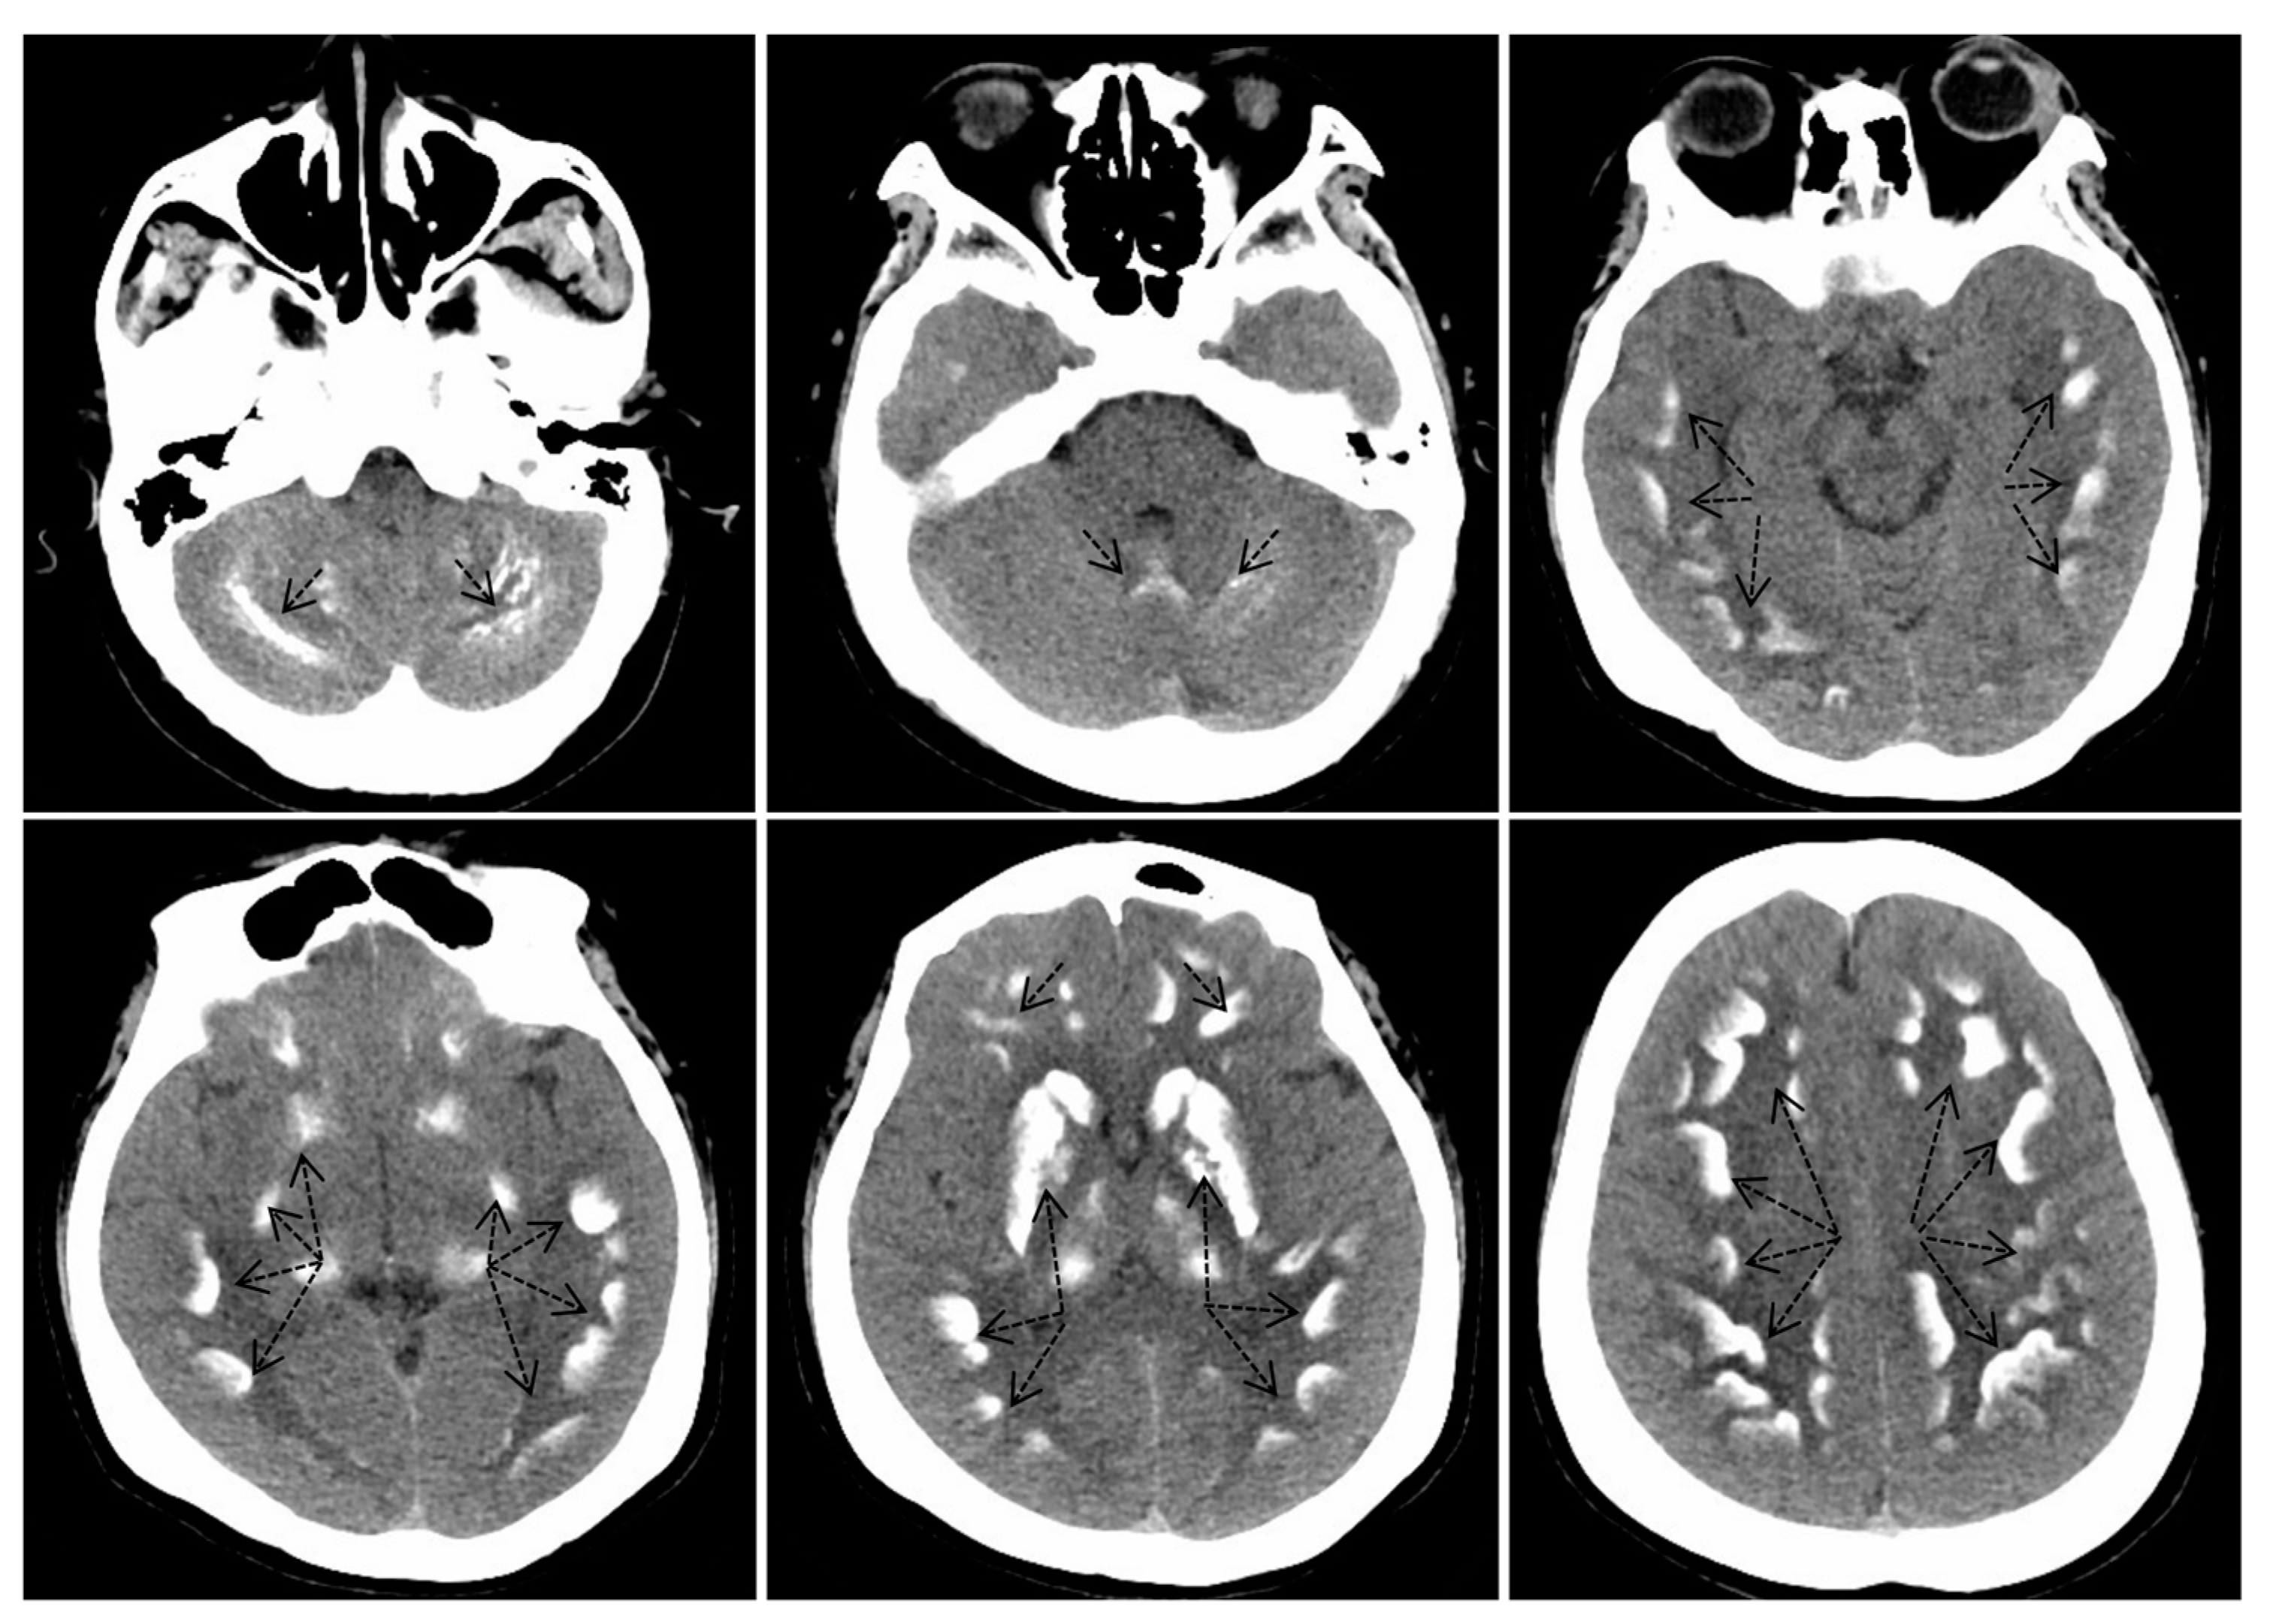

2.2. Biochemical and Radiographic Analysis